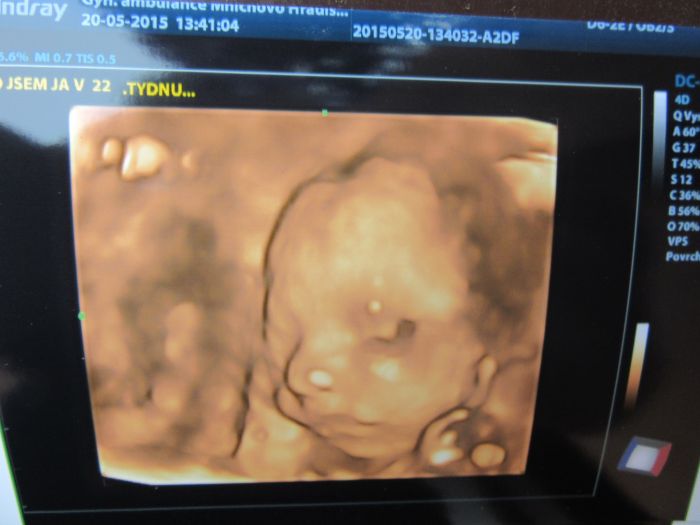

Ahojky, tak dneska jsme byli s manželem na 3D a máme potvrzenou malou fešandu. I přesto, že jsme si přáli kluka tak nakonec jsem spokojená, že to bude holčička. Doktor nám taky řekl, že je vše v pořádku a to je to hlavní. Přikládám fotečky, jsem z malý opravdu nadšená.

[744686] jakoby se na tebe divala, krásné!

kacenko to je fakt nadherna fotecka ,jak je tam krasne videt no uzasny:-) gratuluji k holcicce